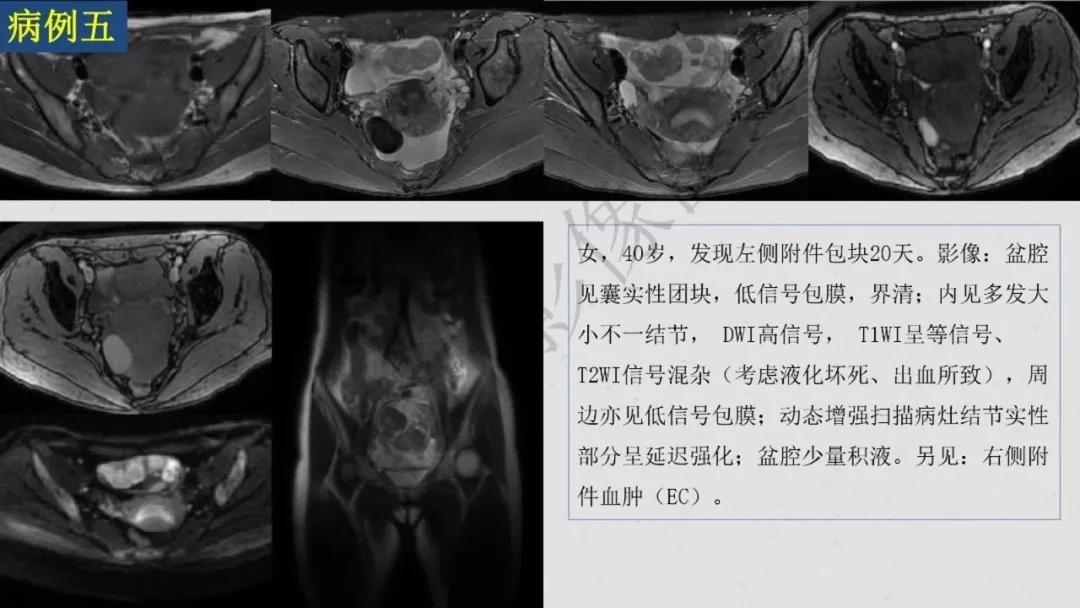

性索间质性肿瘤:较少见,良性多,多数肿瘤具有内分泌功能,可伴有内分泌症状及子宫内膜增生,内膜癌,乳腺疾病。多呈囊实性及实性肿块,界清,形态规则或欠规则,少有壁结节,多数呈实性伴有大片变性低密度改变,轻中度强化。

- 囊实性无壁结节:最常见于颗粒细胞瘤

病理:颗粒细胞瘤